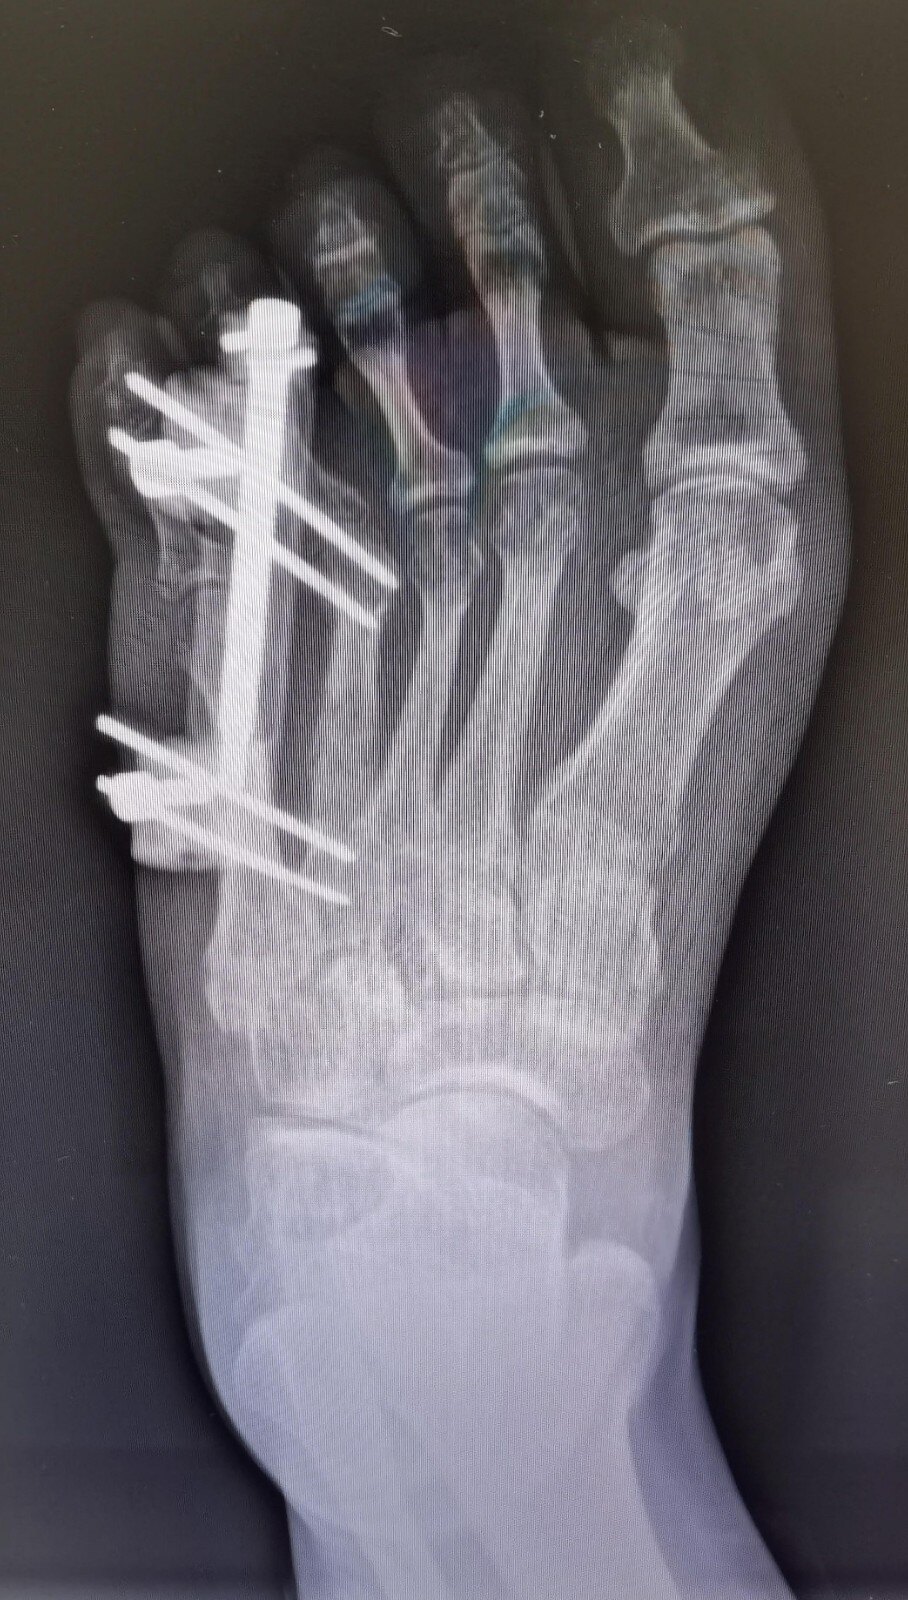

第四足趾短小症短趾症治疗过程

图片尺寸1280x1706